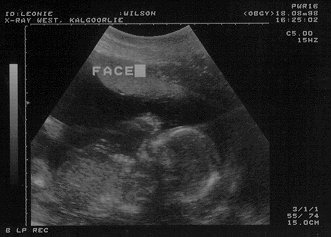

Yesterday we went to have an ultrasound for Leonie. It was arranged that we could take a video along and they'd put it on that for us, but when I got home last night, it was blank - the thing hadn't recorded! So, all I have is the half-dozen prints they gave us. Here is what I think was the best one.

The one burning question was perhaps answered at this session - from what we saw it looks like the baby is a boy (well, they looked like "dangly bits" to me!). Now Leonie is not too happy about this - she wanted another daughter. I'm not fussed, the baby looked healthy and thats what's most important. And I guess Leonie will come 'round eventually. I hope.